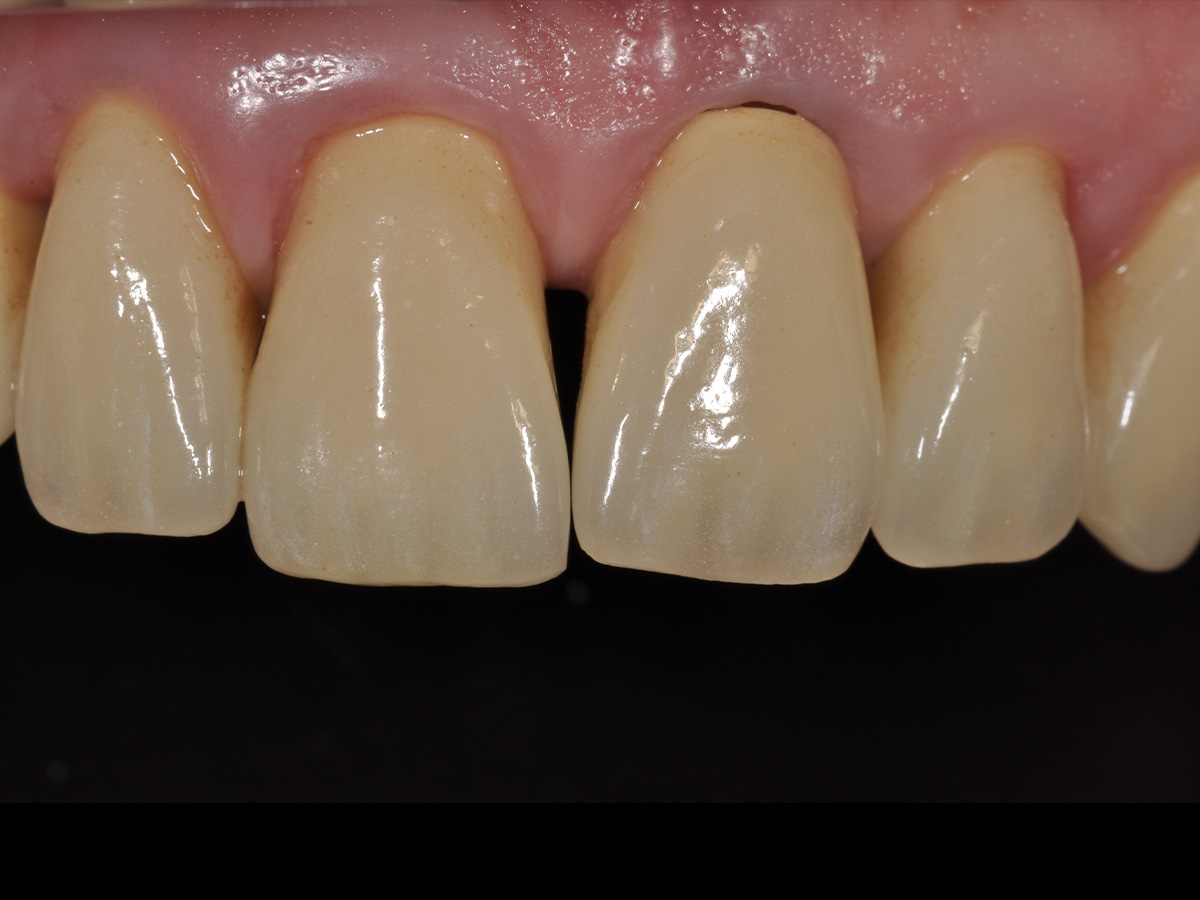

Abbildung 11

Zustand 5 Monate nach Augmentation, Lamina noch vollständig erhalten.